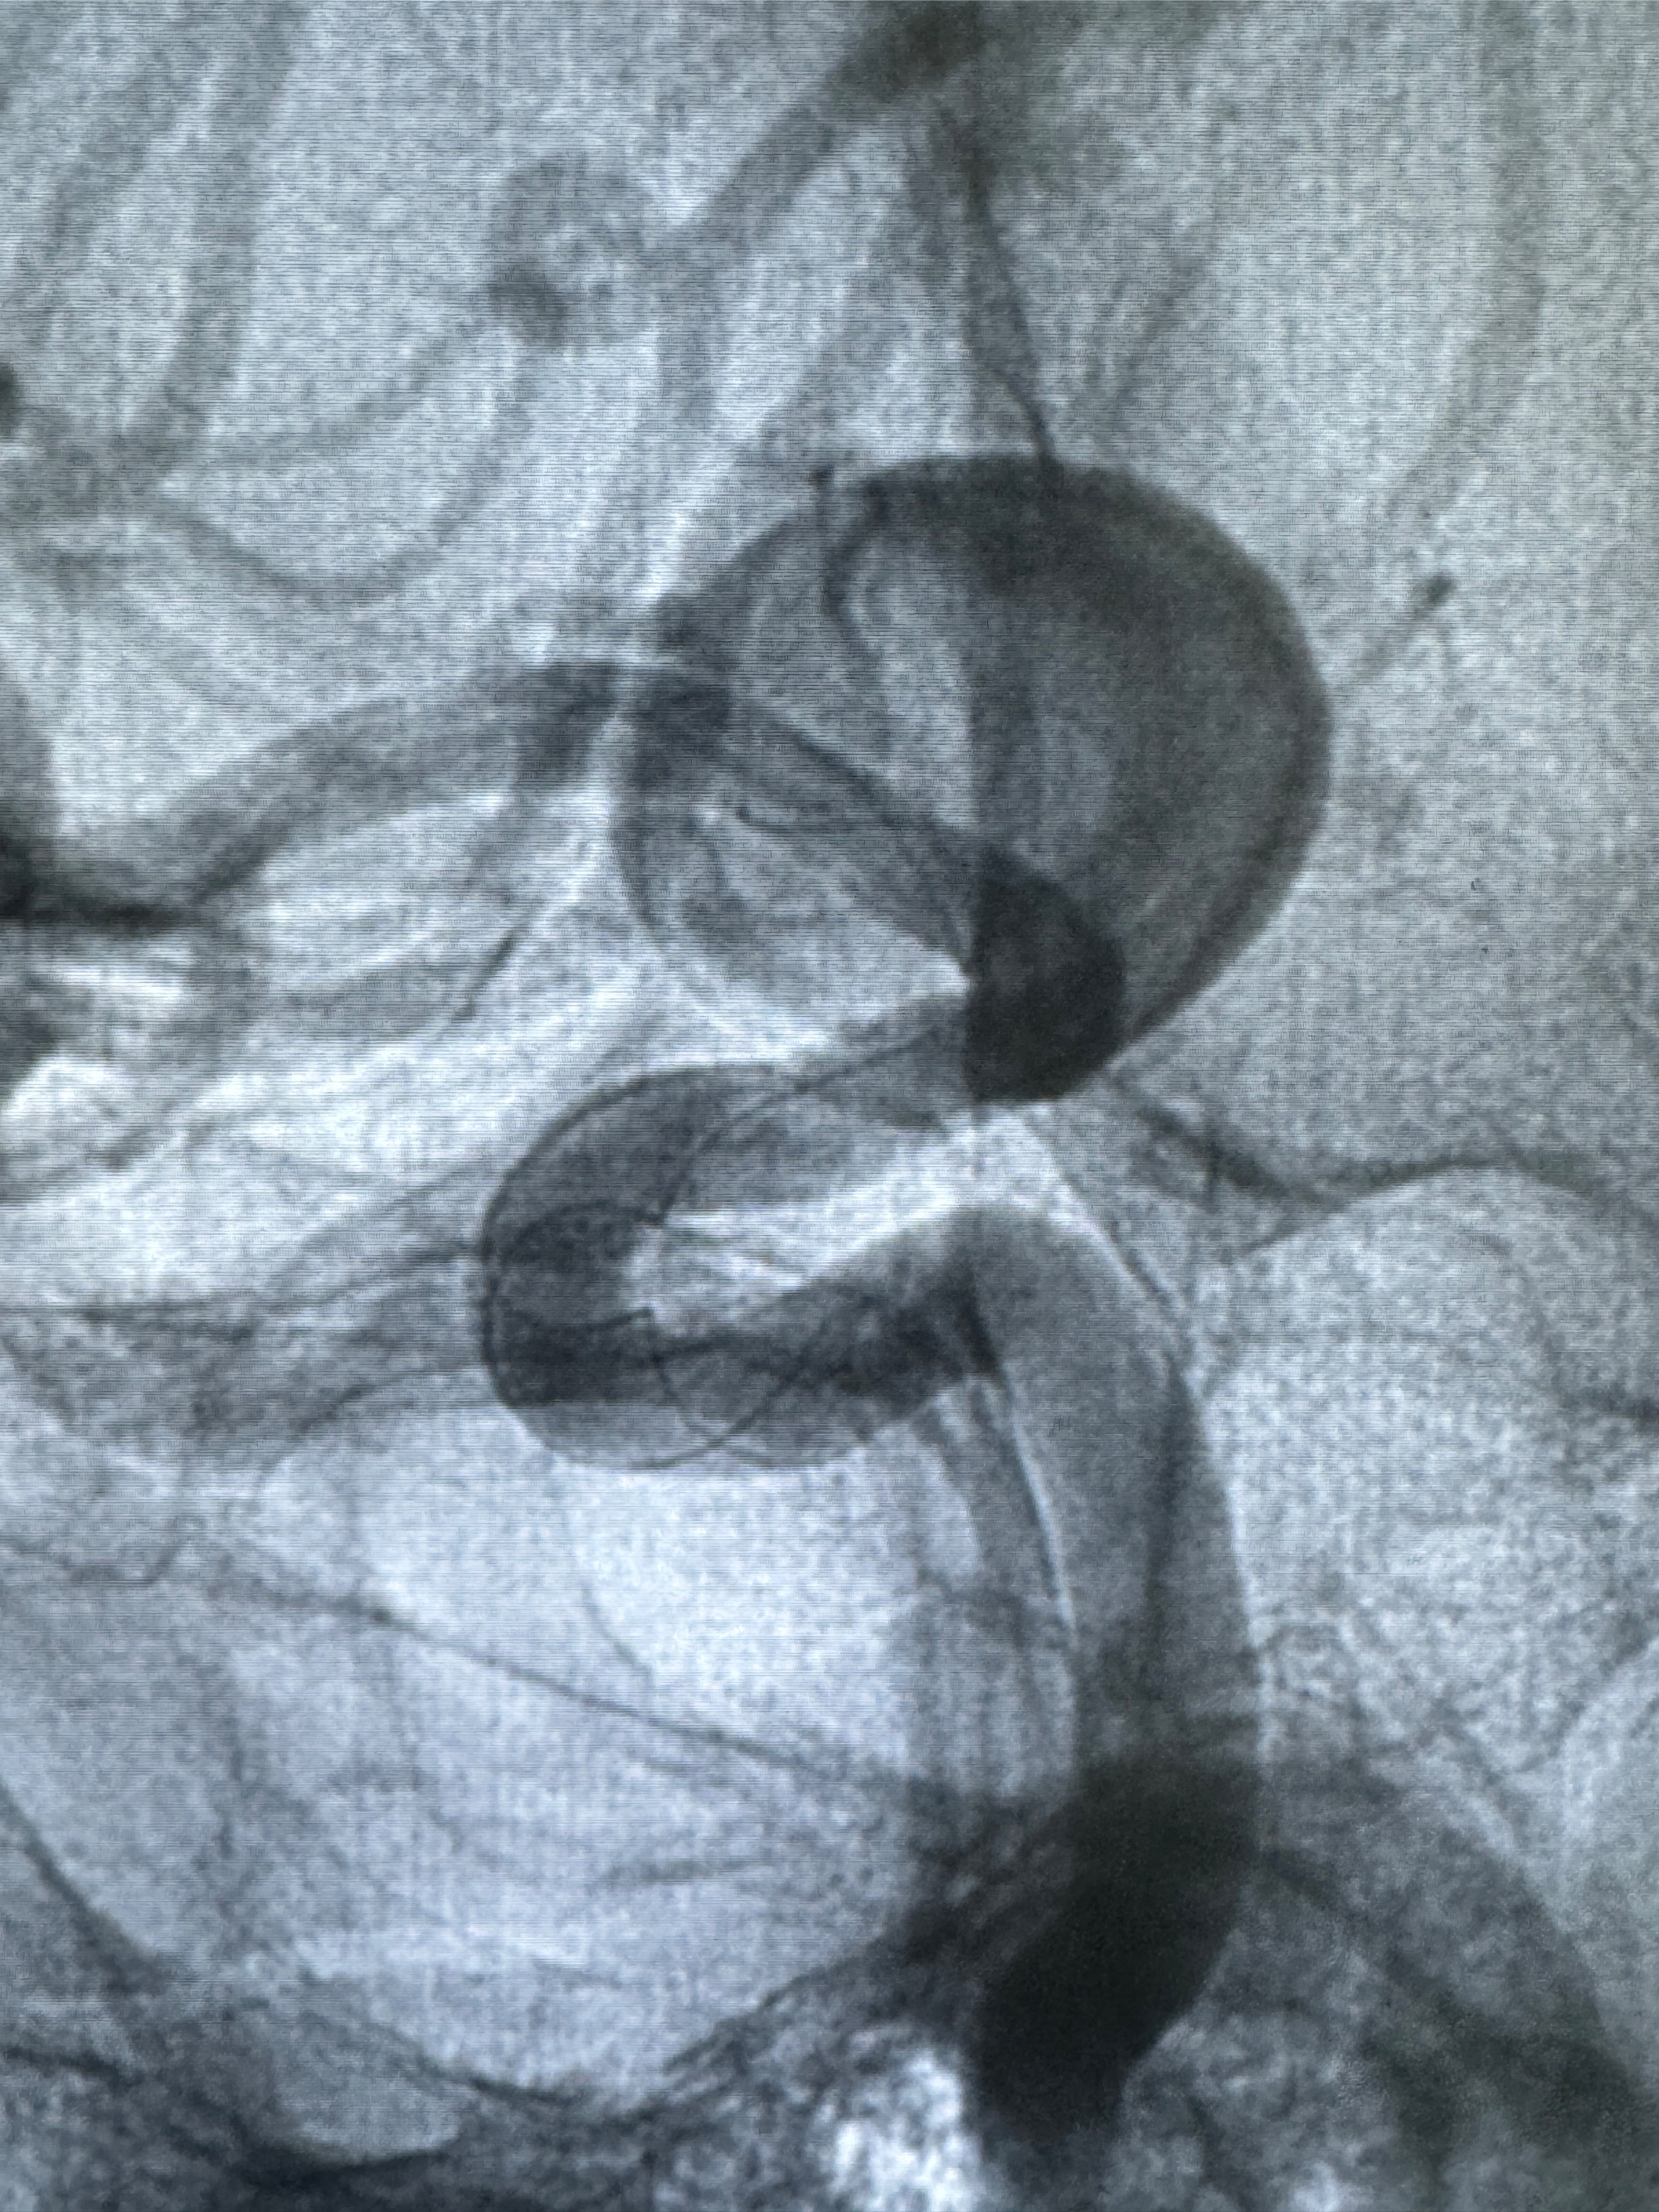

旋转3D展示动脉瘤局部的血管构筑

测量动脉瘤的大小:16*13.8*7.6mm大小,较原先变大,考虑双抗后瘤内血栓溶解可能

观察动脉瘤腔内的血流动力学情况

多角度显示支架打开情况

造影显示支架贴壁情况

再次造影确认支架贴壁情况